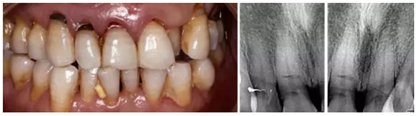

1.臨床病例:患者,男,年齡73歲,不慎摔倒至右上頜側(cè)切牙、左右上頜中切牙外傷根折,X線檢查:12、11、21折裂線達牙頸部以下。CBCT檢查:12、11、21折裂線呈水平狀,達牙頸部以下。

2.診斷:左上頜側(cè)切牙、左右上頜中切牙根折

(1)拔牙后PRF復(fù)合GBR技術(shù)行位點保存